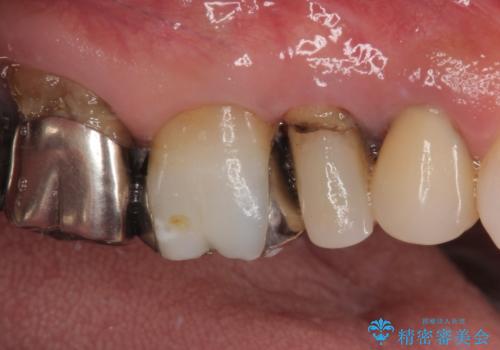

- むし歯の放置期間が長く、クラウンの幅が狭くなってしまった歯を気にして来院された患者様です。

細長いクラウンの周りが汚れてきたこと、奥の銀歯が笑ったときに見えることから、3本をセラミッククラウンにて補綴し、大きさのバランスを整えることとしました。